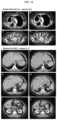

FIG.18. CT response assessment in 2 of 3 patients with >30% reduction in target lesions.Patient 22 is a 65-year-old woman with poorly differentiated SCLC (Trop-2 expression by immunohistology, 3+) who had received 2 months of carboplatin/etoposide (topoisomerase-II inhibitor) and 1 month of topotecan (topoisomerase-I inhibitor) with no response, followed by local radiation for 6 weeks (3000 cGy), but progressed. Four weeks later, the patient started sacituzumab govitecan at 12 mg/kg (2 doses), which was reduced to 9.0 mg/kg (1 dose), and finally to 6.75 mg/kg for 9 doses. The patient presented initially with the sum of the longest diameters (SLD) of the target lesions totaling 19.3 cm. Two of the target lesions showing the best shrinkage are shown at baseline (A and C). After 4 treatments, she had a 38% reduction in target lesions, including a substantial reduction in the main lung lesion (5.8 to 2.7 cm; panels B and D). On hernext CT assessment 12 weeks later, the patient progressed. Patient 3 a 62 year-old woman, who 5 months after her initial diagnosis and surgery for colon cancer had a hepatic resection for liver metastases and then received 7 months of treatment with FOLFOX and 1 month of only 5-fluorouracil. She was referred to the sacituzumab govitecan trial with multiple lesions, primarily in the liver (left panels A, C, and E). Immunohistology showed a 2+ staining of her primary cancer; her plasma CEA was 781 ng/mL. Therapy was initiated at 8 mg/kg and 6 treatments later (12 weeks), the 3 target lesions had reduced from 7.9 cm to 5.0 cm (−37%; PR). The response was confirmed 6.6 weeks later (after ten doses), with additional shrinkage to 3.8 cm (−52%). Panels B, D, and F show the shrinkage of these 3 lesions (59% reduction at this time) 32 weeks from the start of treatment and after receiving 18 doses The patient continued therapy, achieving a maximum tumor reduction of 65% 10 months after treatment was initiated (28 doses). Plasma CEA decreased to 26.5 ng/mL after 18 doses, but thereafter began to increase despite continued radiological evidence (target and non-target lesions) of additional disease reduction or stabilization. Approximately 1 year from the start of treatment (31 doses given), one of the 3 target lesions progressed.